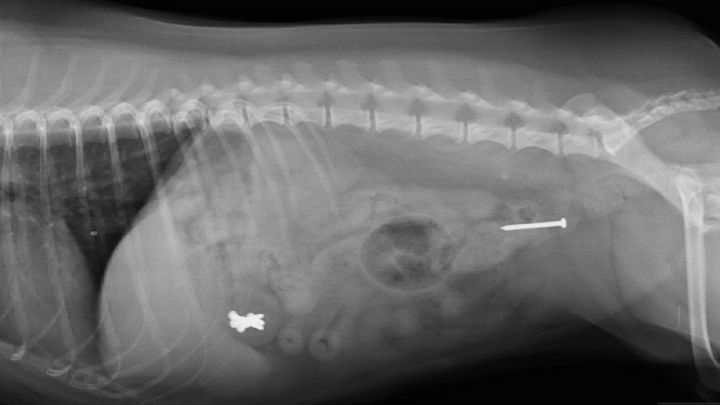

I then took Clarice to the vet for an Xray which revealed 6 nails stuck inside her stomach and 1 somehow luckily on its way out. The option to leave then in her stomach and hope for a safe exit is too risky due to the sharp nails possibly puncturing holes inside her body. Surgery is the only reasonable option.